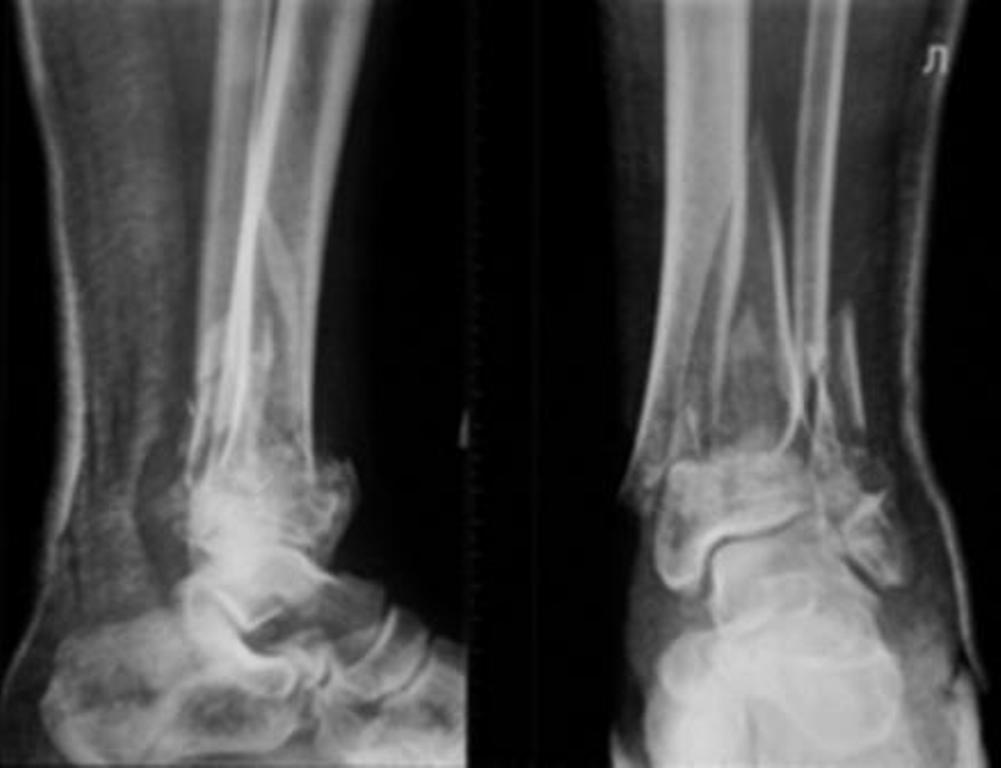

Re: Перелом дистального отдела костей голени

До лечения, в процессе, через 8 мес.